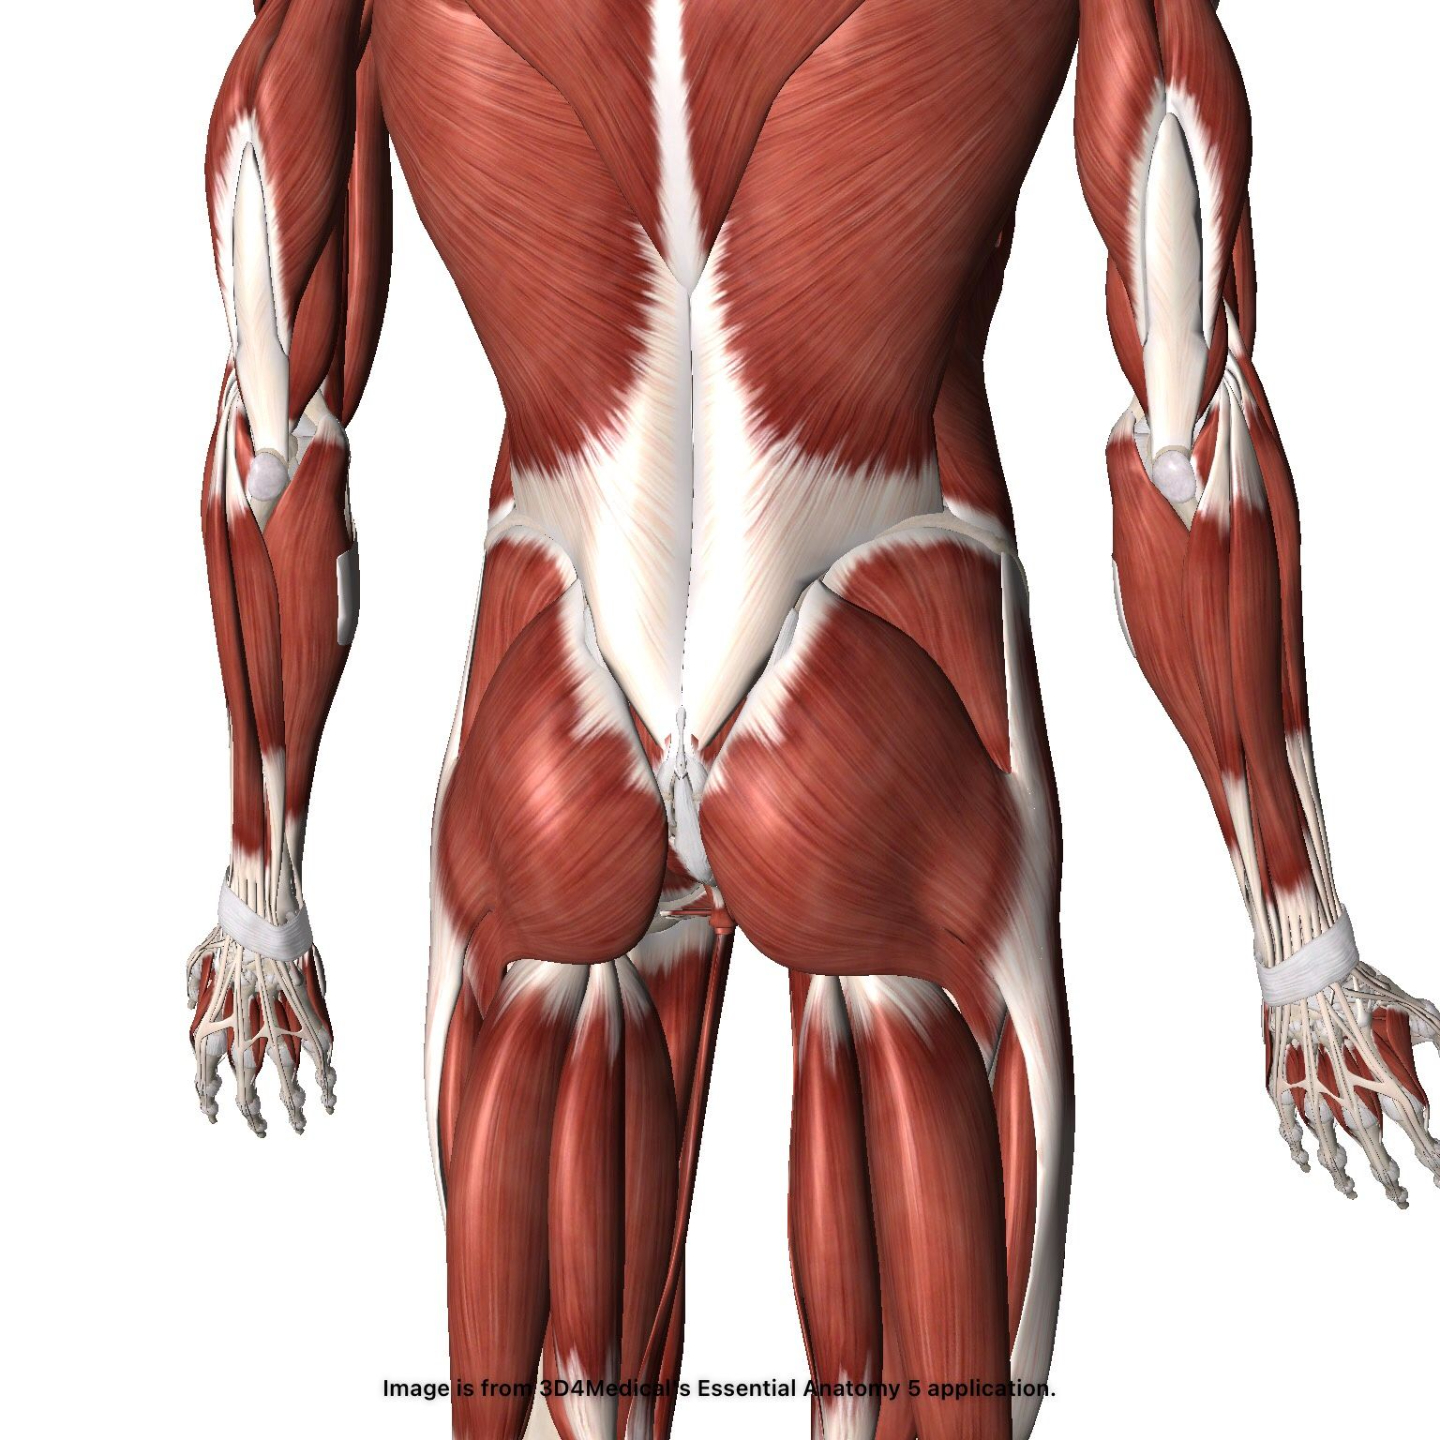

Back Injuries

Check out our one-of-a-kind diagnostic dashboard! Learn more about multiple orthopedic back injuries - the who, what, when, where, and how's.

Diagnostic Dashboard

Spondylolysis

Low Back Pain